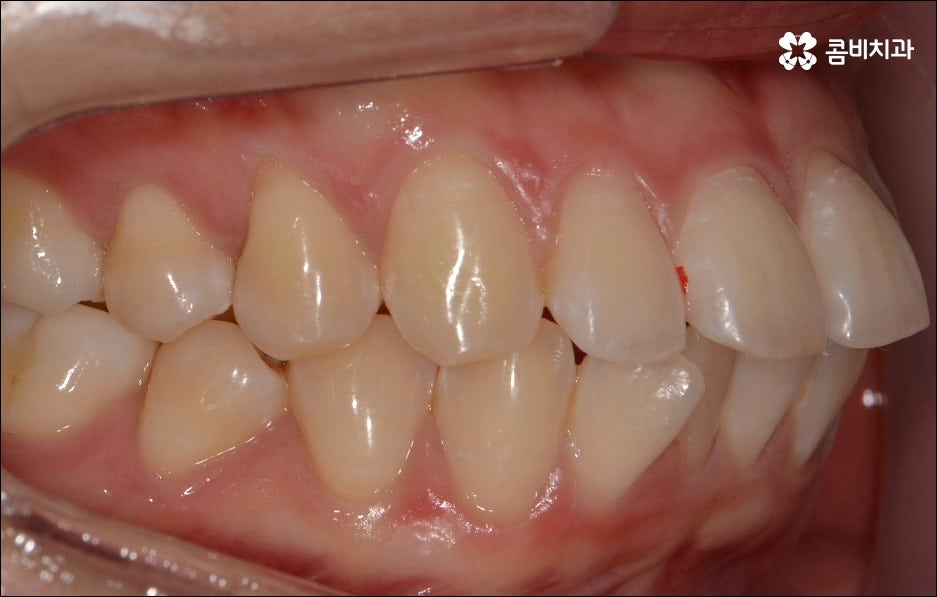

치열이 불규칙하여 기능적 심미적인 불편을 겪는 분들 중에 교정 치료를 고민하시는 분들이 많이 있습니다. 특히 앞니는 다른 치아보다 훨씬 외부에 잘 드러나므로 대화하거나 웃을 때 만약 앞니 사이가 벌어져 있거나 앞니 돌출 이 된 경우, 비틀어진 경우에는 신경이 많이 쓰일 수 있는데요. 하지만 막상 교정을 시작 하려고 하면 기간이 오래 걸리는 것 때문에 또는 치료 과정 자체에 부담을 느껴서 망설이시는 분들도 있을 수 있어요. 이때 앞니 외 다른 치아 배열 또는 위아래 교합에는 별다른 이상이 없다면 문제가 있는 앞니만 부분교정으로 치료할 수 있으니 이에 대해서 한 번 알아보시면 도움이 되실 거예요.

부분교정은 짧은 기간에 모든 치아가 아닌 특정 치아만 집중적으로 교정하는 것으로, 예를 들어 앞니 돌출 을 개선하기 위해 앞니와 그 옆의 치아까지 6~8개의 치아에만 브라켓을 장착하여 교정 치료를 하는 것을 의미하고 있어요. 비교적 간단한 과정이라고 생각하실 수 있으나 다른 치아에는 영향을 주지 않으면서 주변 치아와 앞니의 이동량을 고려하여 교합을 세밀하게 조정하고 전체 균형을 맞춰나가야 하는 만큼 의료진의 높은 숙련도가 필요한 과정이라고 할 수 있는데요.

만약에 앞니 돌출 이 각도만의 문제라면 이를 교정하기 위한 치료는 좀 더 간단하게 끝날 수 있습니다. 말씀드렸던 것처럼 상황에 따라 보다 빠른 부분교정을 통해 앞니만 교정 치료를 진행할 수도 있을 거예요.

하지만 보통은 돌출된 앞니 뿐 만 아니라 골격적인 부분이 원인이 되는 경우가 많으며 이런 경우에는 상태에 맞게 전체적으로 교정을 진행하여야 교합이 올바르게 되고 입매가 전체적으로 균형감 있게 개선될 수 있어요. 이런 경우에 골격적인 원인을 무시한 채 무리하게 치아의 각도만 안쪽으로 넣으려고 하면 자칫 옥니가 될 수도 있기 때문에 이러한 부작용을 막기 위해서도 환자분들의 상황을 정확하게 검진하고 그에 맞는 교정 플랜을 세우는 것이 필요한 거예요. 물론 부정교합 정도가 심각하고 골격적인 원인이 이미 굳어진 경우와 같이 수술이 함께 필요한 케이스도 있을 수 있으나 교정 치료만으로도 튀어나온 앞니가 들어가면서 자연스럽고 부드러운 인상으로 바뀌는 경우도 많으니 먼저 검진과 상담부터 꼼꼼하게 진행해 보시길 권유드리고 있습니다. 특히 개개인의 치열, 교합, 잇몸 상태, 구강구조 등을 면밀하게 파악하고 그에 따른 정확한 치료 계획을 수립할 수 있는 경험 많은 의료진과 함께 하는 것이 중요할 수 있어요.